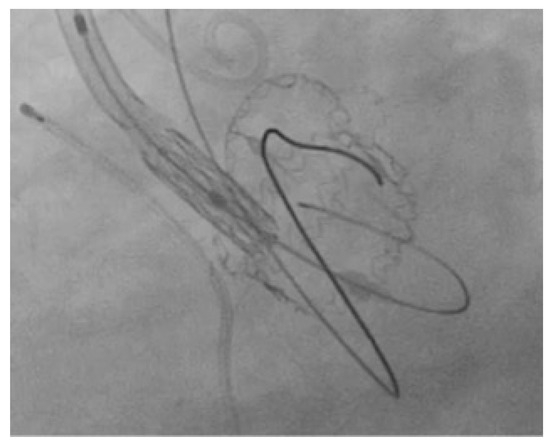

2.2. Technology

2.3. VIV-TAVR Planning and Technical Procedures